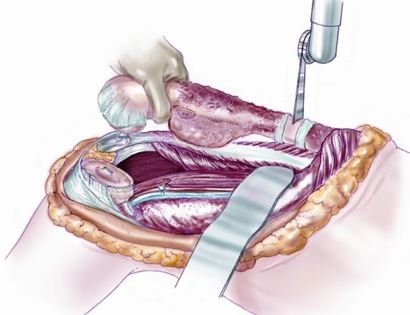

Bone Sarcoma Removal Video

Dr. James Wittig narrates a video illustrating the surgical technique for the resection of a bone sarcoma. | WATCH VIDEO